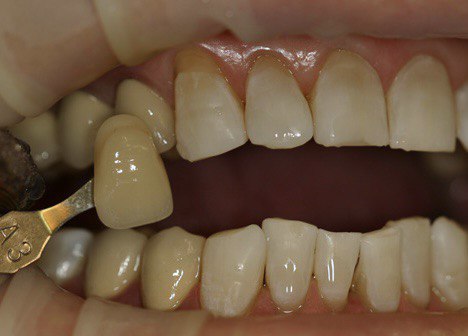

До процедуры цвет зубов А3 по шкале VITA, после процедуры цвет зубов В1 по шкале VITA.

Пациенту рекомендована замена коронок на жевательных зубах, так как они не соответствуют цвету отбеленных зубов.

Примечание: необходимо помнить, что после отбеливания и достижения желаемого результата, может потребоваться замена реставраций (пломб, коронок, виниров), так как их цвет может быть гораздо темнее отбеленных зубов!

Результат лечения